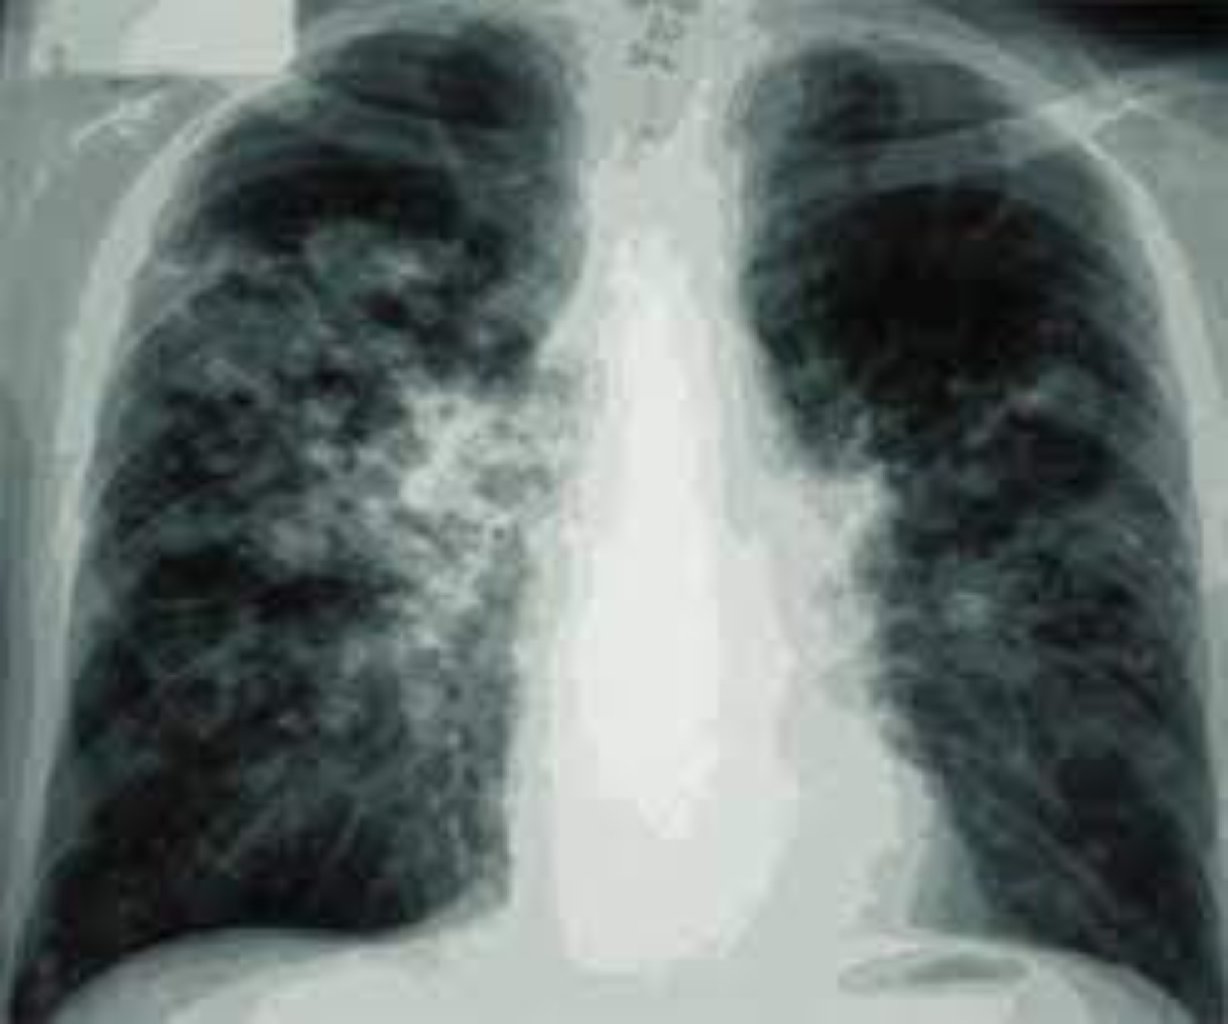

Pnevmoniyanın Səbəbləri və Risk Faktorları Mikroorqanizmlər: Bakteriyalar (məsələn, Streptococ ...

Vərəmin Səbəbləri və Yoluxma Yolları Yoluxma Yolu: Vərəm, yoluxmuş bir şəxsdən başqasına, öskü ...